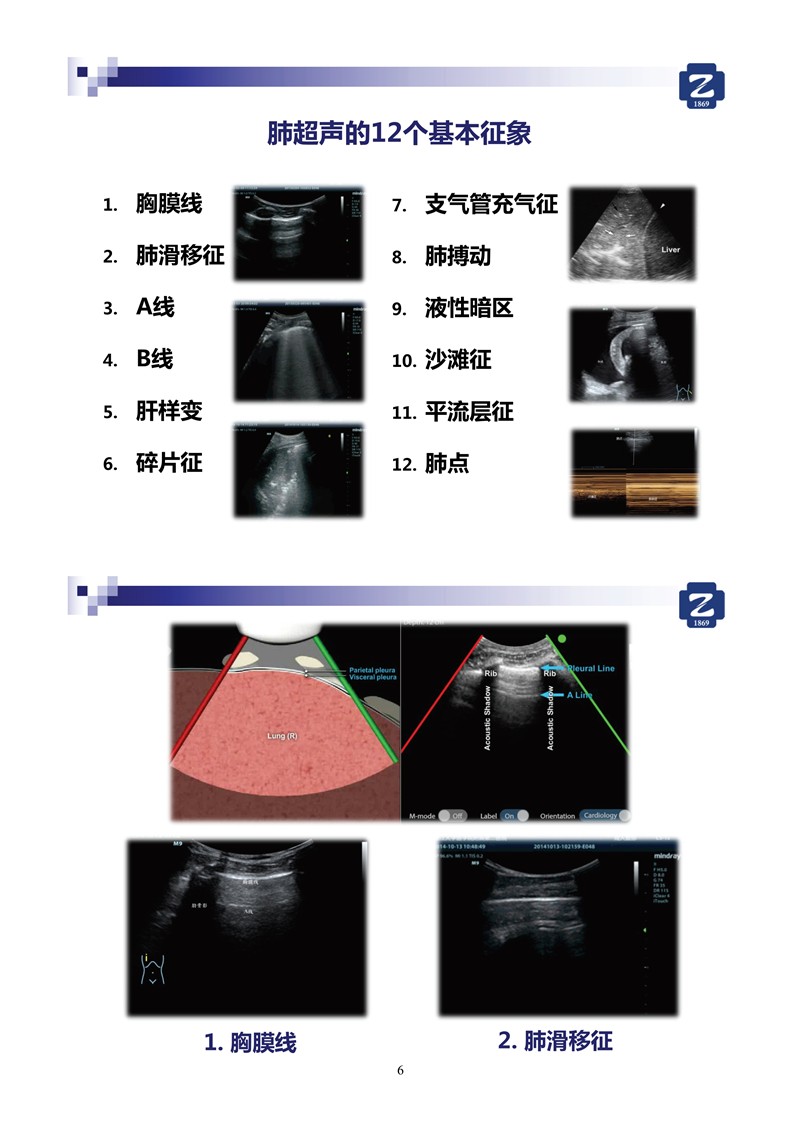

第二版新型冠狀病毒肺炎超聲診斷實(shí)用手冊(cè)_2.jpg

第二版新型冠狀病毒肺炎超聲診斷實(shí)用手冊(cè)_64.jpg